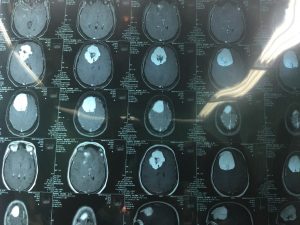

اعلن باسم حنون جبار مدير مستشفى العلوم العصبيه التابع لدائرة صحة بغداد الرصافة عن قيام فريق طبي بإجراء عمليه جراحيه خطيرة لرفع ورم سحائي من الدماغ , وكان الفريق الطبي برئاسة وسام جاسم الربيعي وبين ان المريضه راجعت المستشفى وكانت تعاني من نوبات صرع متكررة وصداع حاد مزمن وبعد اجراء الفحوصات اللازمة واخذ اشعة الرنين المغناطيسي تبين وجود ورم كبير حجم 8×7 سم متواجد في الفص الامامي والجداري الايمن للدماغ مؤثرا على الحركة للجهة اليسرى من الجسم , مؤكدا الربيعي انه في حالة عدم ازالت هذا الورم سوف يؤدي مستقبلا الى فقدان الحركة للجهة اليسرى للمريضة علما انها تبلغ من العمر 45 سنه ومن سكنه محافظه كربلاء منوها ان العمليه استغرقت 3 ساعات متواصلة وأخرجت بعدها المريضة ووضعها مستقر والحمد لله .

مضيفا يوجد ورم ثاني في الفص الامامي الايسر للدماغ ولكن حجمه اقل وسوف يتم معالجته عن طريق اشعة الكاما نايف بعد اكتساب المريضة الشفاء التام واستقرار حالتها الصحية .